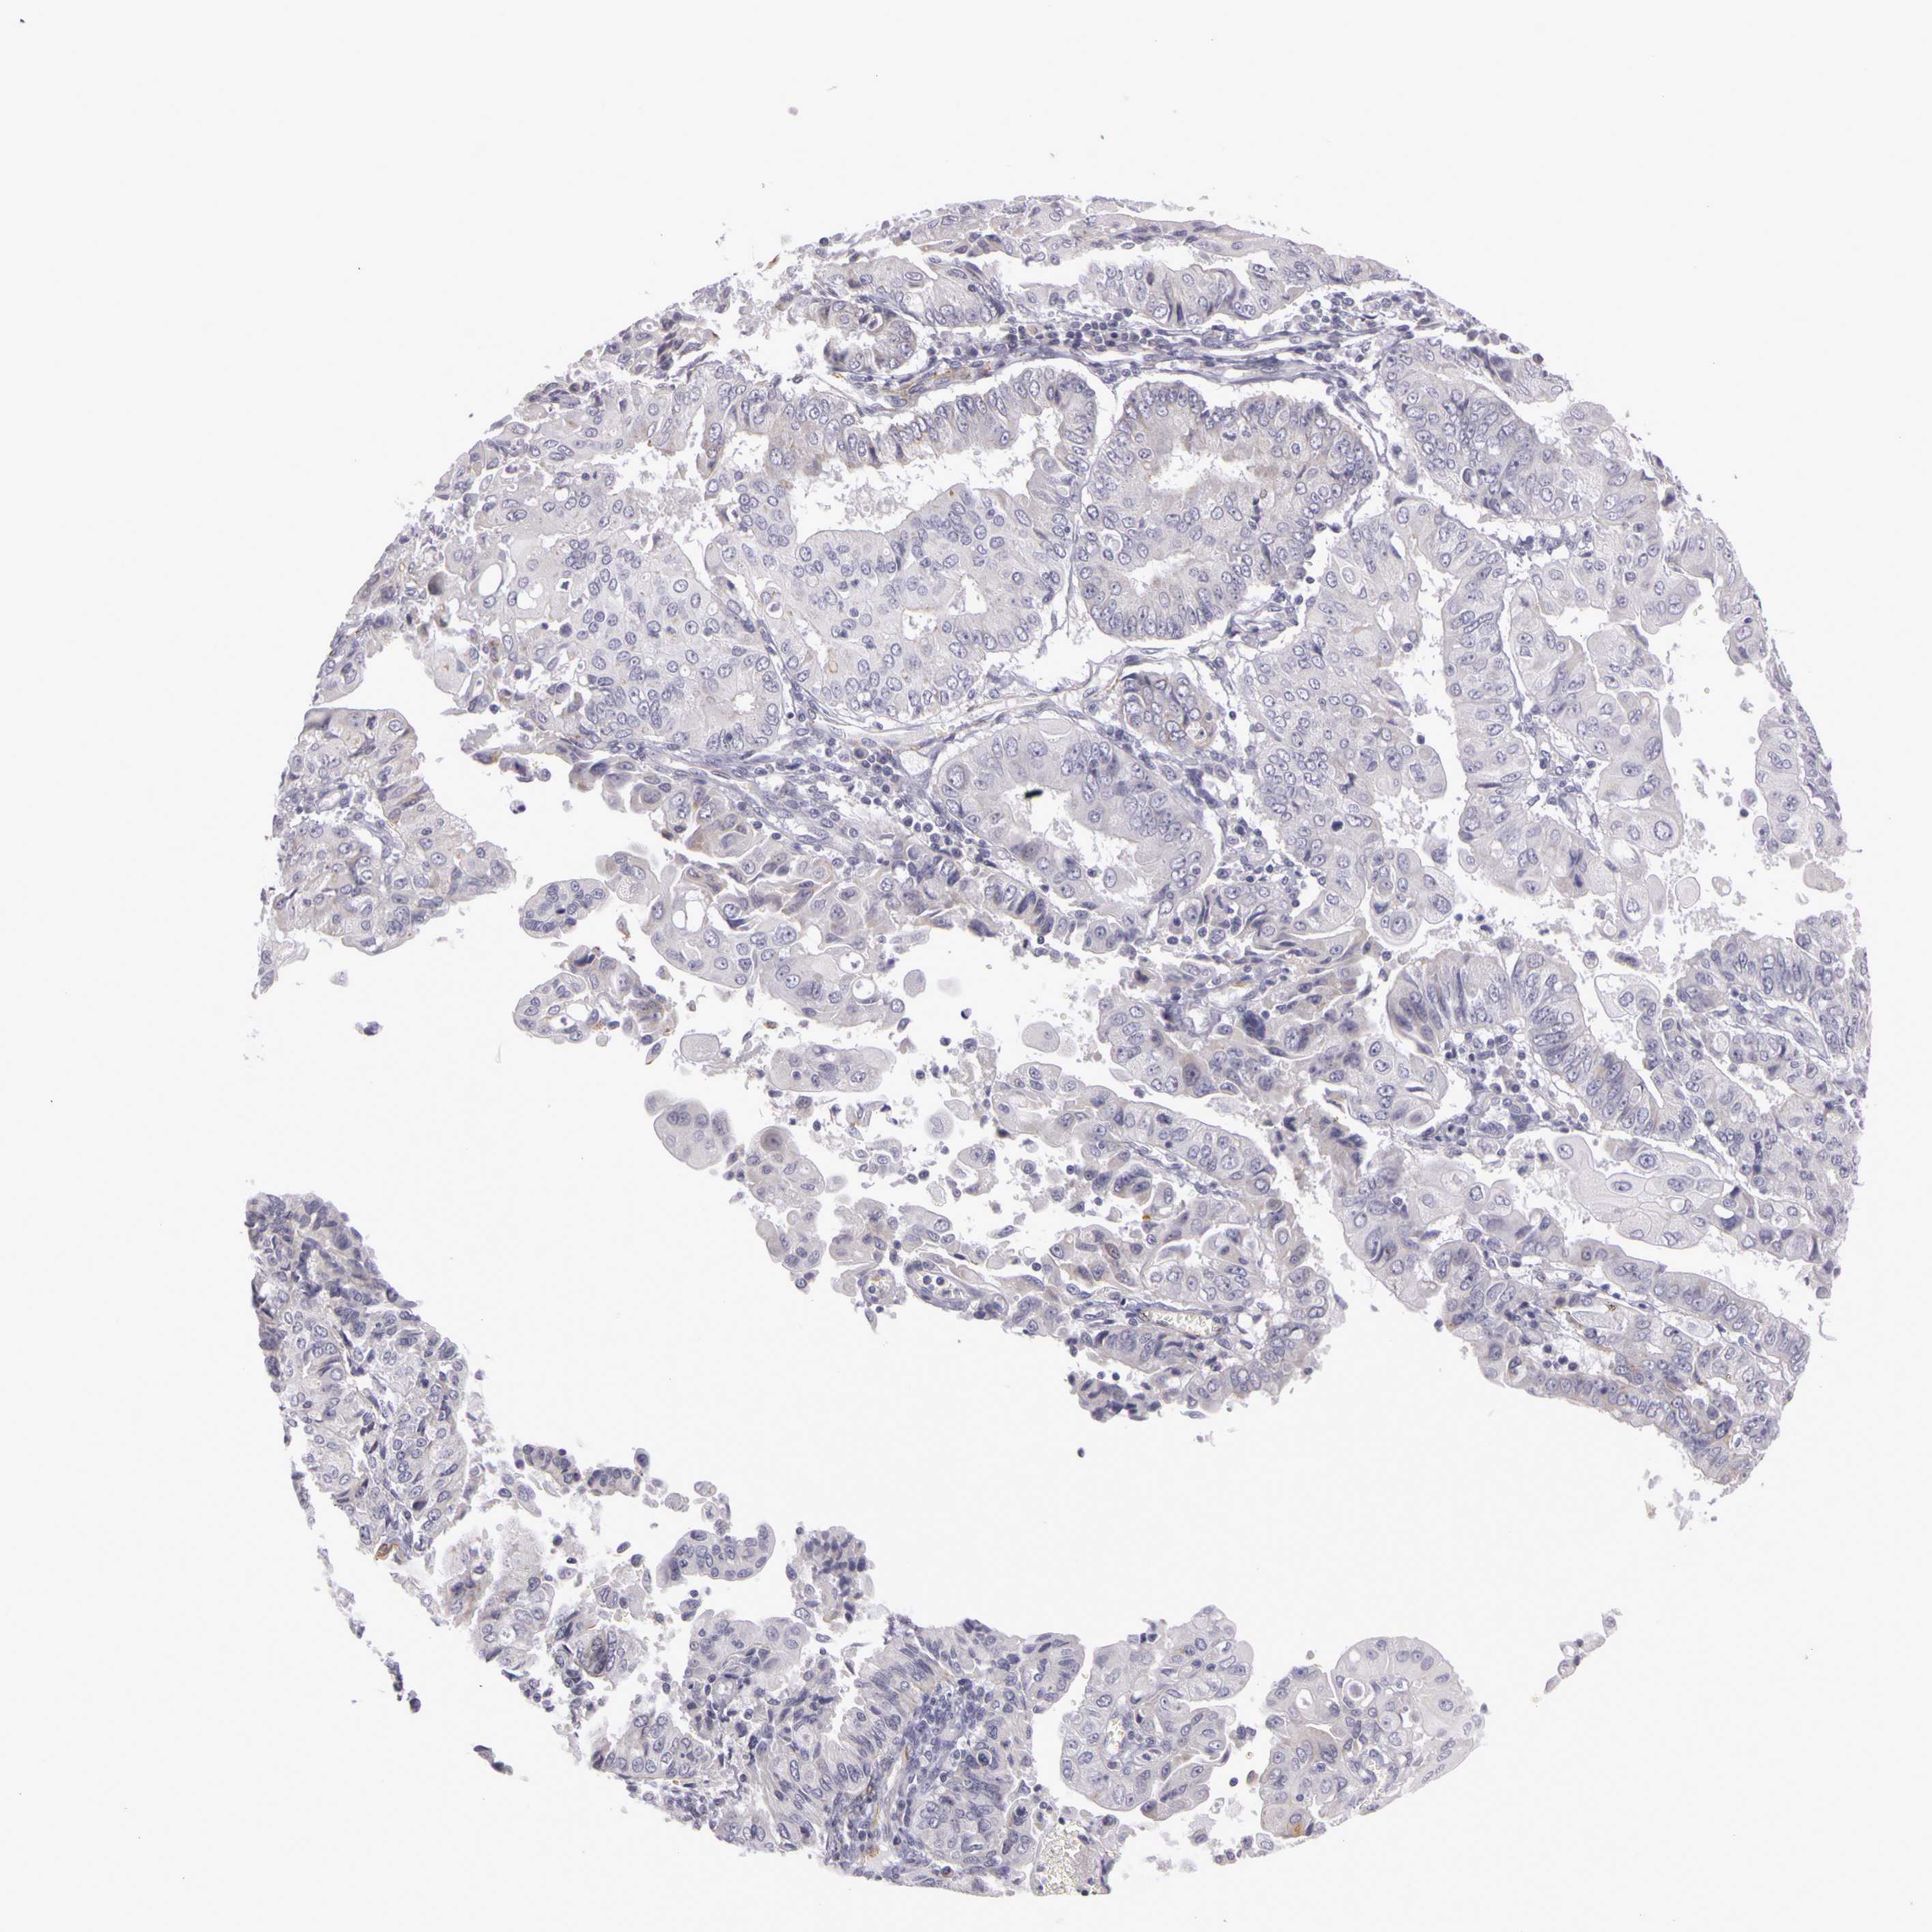

ENDOMETRIAL CANCER - Protein expressioni

A mouse-over function shows sample information and annotation data. Click on an image to view it in a full screen mode. Samples can be filtered based on level of antibody staining by selecting one or several of the following categories: high, medium, low and not detected. The assay and annotation is described here.

Note that samples used for immunohistochemistry by the Human Protein Atlas do not correspond to samples in the TCGA dataset.

Antibody stainingi

Antibody staining in the annotated cell types in the current human tissue is reported as not detected, low, medium, or high, based on conventional immunohistochemistry profiling in selected tissues. This score is based on the combination of the staining intensity and fraction of stained cells.

Each image is clickable and will lead to virtual microscopy that enables deeper exploration of all samples and also displays staining intensity scores, fraction scores and subcellular localization as well as patient and tissue information for each sample.

Antibody HPA001397

Antibody HPA012497

Staining

High

Medium

Low

Not detected

Intensity

Strong

Moderate

Weak

Negative

Quantity

>75%

75%-25%

<25%

None

Location

Nuclear

Cytoplasmic/membranous

Cytoplasmic/membranous,nuclear

Adenocarcinoma, NOS